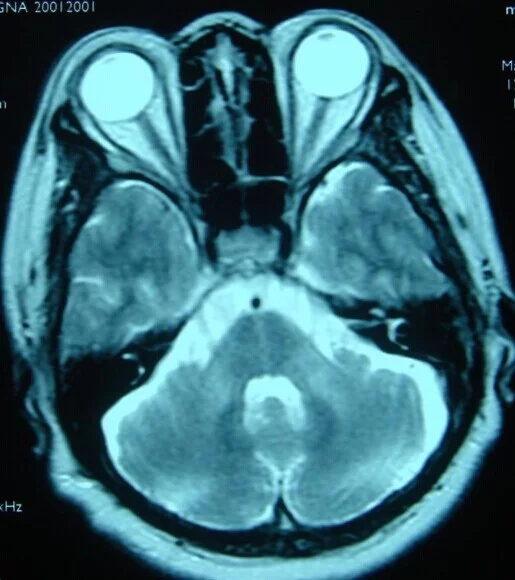

⑵橄榄小脑桥脑萎缩(OPCA):常染色体显性遗传,中年后起病,除小脑型共济失调和构音障碍外有早期尿失禁,部分病人有智能减退和锥体外系症状如帕金森综合征等,但无眼球震颤。

2.头颅MRI对OPCA有确诊价值。